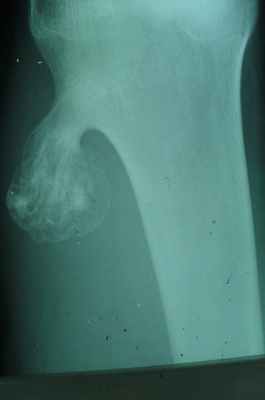

Рис. 3. Гиперостоз бедренной кости.

Гиперостоз - как правило, вторичный процесс. Причиной его может быть воспаление, травма, нарушение гормонального статуса, хроническая интоксикация (мышьяком, фосфором) и др. Первичный гиперостоз наблюдается при врожденном гигантизме.

Рис. 4. Гиперостоз и склероз большеберцовой кости (склерозирующий остеомиелит Гарре).